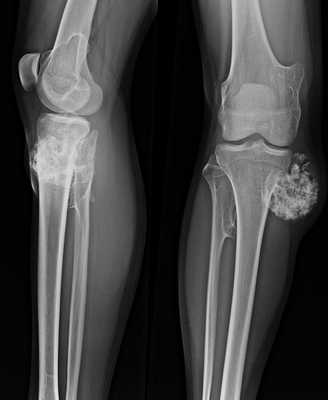

Излюбленным местом локализации патологии является большеберцовая кость в области голени. Наросты при экзостозе большеберцовой кости часто достигают больших размеров и сдавливают нервные волокна, приводя к развитию болевого синдрома. Примерно в 5-10% случаев заболевание развивается непосредственно внутри сустава.

Следующим по частоте возникновения является поражение малоберцовой кости. Обычно новообразования формируются в ее верхней трети, патология часто сопровождается сдавливанием малоберцового нерва и умеренной болью под коленом.

При экзостозе бедренной кости разрастания часто локализуются в области тазобедренного сустава и приводят к существенному ограничению подвижности даже при небольшом размере. У некоторых пациентов диагностируется костно-хрящевой экзостоз медиального мыщелка, при котором наросты формируются в дистальном отделе нижней части бедра. Патология сопровождается дискомфортом в колене и затруднением сгибательно-разгибательных движений.

В нашей клинике стандартным методом диагностики является рентгенологическое исследования. На рентгенограммах остеохондромы определяются как локальное выбухание кости. Все экзостозы исходят из кости на узкой или на широкой ножке. От этого зависит эволюция остеохондром и выбор тактики лечения.

Основным методом диагностики является рентген в 2-х проекциях. На снимках визуализируется только костная часть опухоли в виде новообразования с четкими границами и соединенного тонкой ножкой или толстым основанием с материнской костью. Также наблюдается истончение кортикального слоя кости, а сама остеохондрома часто имеет вид «цветной капусты» из-за участков обызвествлений в хрящевой шапочке.